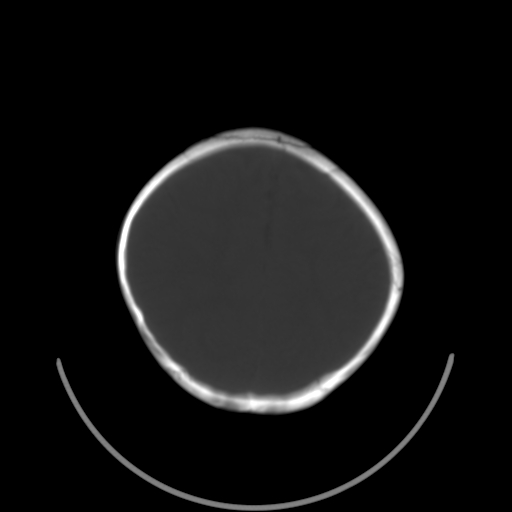

以下是引用深泽交通医院在2009-10-16 8:25:00的发言:[br]右眼环出血伴异物

以下是引用卜一在2009-10-16 15:01:00的发言:[br]右眼球挫裂伤伴异物!

以下是引用拾荒者在2009-10-17 18:38:00的发言:[br]鼻面部皮下积气,右侧睑缘及眼球壁高密度异物影,左侧眼球壁晶状体内侧缘处是圆形低密度影。低密度异物?应提请眼科医生注意。